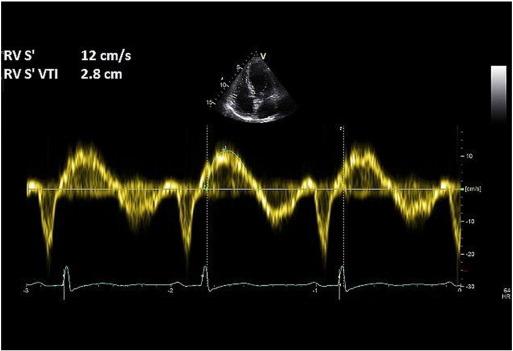

In this fairly new technique, CW Doppler of the TR jet is traced and the mean pressure difference is measured from the velocity-time integral (VTI) (Fig. 5 ). RAP is then added to calculate the mPAP. Mean PAP measured by this method correlates closely with catheter-measured mPAP [22] . The mPAP from TR VTI can be calculated using the following formula: mPAP = meanΔP + RAP.

Fig. 5.

Tricuspid regurgitation velocity-time integral method for measuring mPAP.

5.2. Common pitfalls

A complete TR envelope may not be possible in all patients. Inaccurate RA pressure measurement leads to over or underestimation of mPAP.